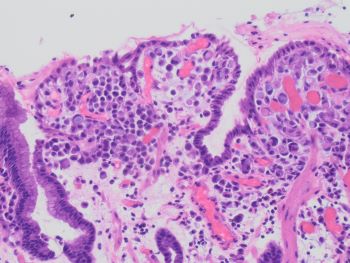

As shown on the H&E, the gastric mucosa shows atypical cells located predominantly in the superficial lamina propria. The atypical cells are small, discohesive cells with targetoid mucin, minimal nuclear atypia without stromal desmoplasia or necrosis. The background mucosa shows mild reactive changes but no intestinal metaplasia.